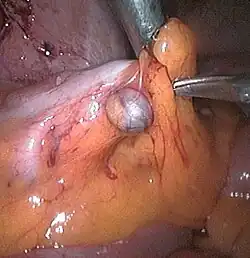

Die Divertikulose ist eine Veränderung des Dickdarms in Form von kleinen Ausstülpungen der Darmwand. Bei diesen Ausstülpungen wird von falschen Divertikeln gesprochen. Falsch werden sie genannt, da hier im Gegensatz zu den echten Divertikeln nur die Schleimhaut und nicht die ganze Darmwand ausgestülpt wird.